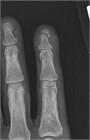

末節骨粗面(Tuft)骨折は多くの場合,指先の挫傷によって生じる.閉鎖性Tuft骨折は鎮痛薬のみで治療できる.疼痛管理には指ブロックと爪下血腫のドレナージを考慮する.開放性Tuft骨折では,鎮痛(たいてい指ブロック麻酔)後の創部観察と広範な洗浄が必要である.爪床の損傷は露出した骨を覆うように縫合すべきである.感染を防ぐには局所の創傷処置が最善であるが,著しい汚染がある場合は短期間の抗生物質投与を考慮する.通常,これらの骨折に副子固定は必要ない.

車のドアを閉める際に挟む等,指先が潰されるように受傷した患者が受診する.指先の腫脹と疼痛があり,斑状出血を伴う.爪下血腫,開放性の爪床損傷,指腹の裂傷を認める場合がある.